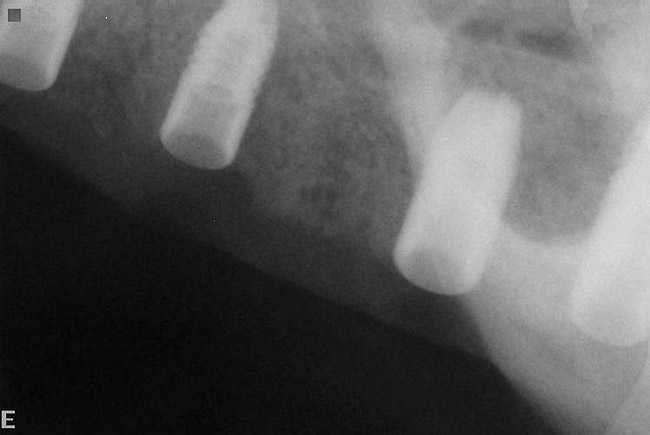

The patient was scanned with a cone beam CT scan while wearing a radiopaque scanning appliance based on her new treatment denture. Horizontal bone augmentation was confirmed radiographically, and both grafted sinuses resulted in satisfactory bone quantity for implant placement. Vertical augmentation was not attempted because of the patient’s unwillingness to forego her removable prosthesis for any period of time. Therefore, shorter implants were treatment-planned, resulting in the placement of eight implants, rather than fewer—such as six—implants, to support a full-arch fixed prosthesis. Because adequate bone and keratinized mucosa were present, a flapless, computer-guided implant insertion was performed (Figure 18). After removal of the surgical guide, placement of all eight implants could be inspected (Figure 19). Post-placement periapical radiographs are shown in Figure 20 and Figure 21.

Figure 20  Post-placement periapical radiographs.

Figure 20

Figure 21  Post-placement periapical radiographs.

Figure 21